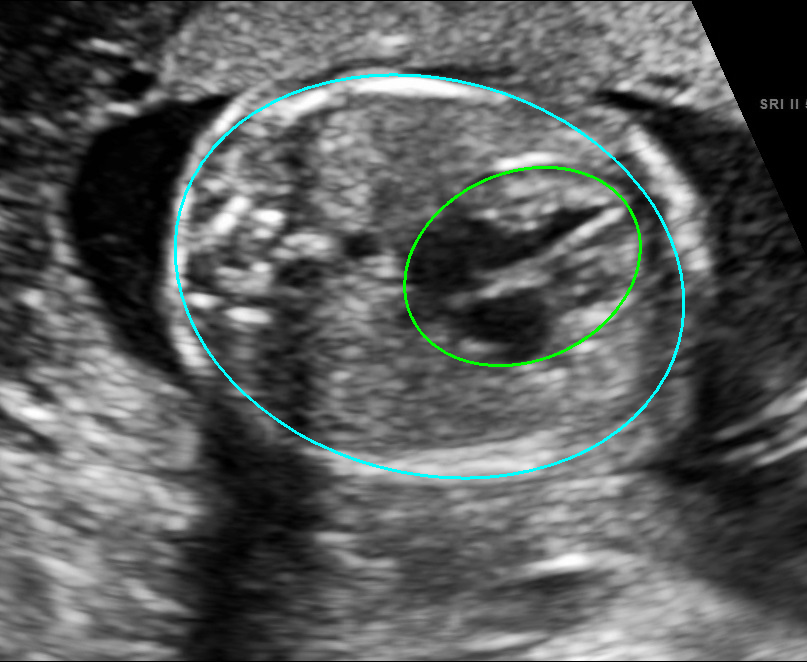

Visualization results of different methods.

Although the segmentation model trained on the fetal ultrasound dataset achieves a relative high average dice scores averaging over 0.9, the fitted ellipse highly depends on the segmentation results. As shown in the middle row of Fig. 2, the segment-based ellipse-fit method performs well when the image quality is good (first row), but the performance degrades when the segmentation is affected by image artifacts such as the acoustic shadowing (second and third row). Our proposed method is more robust to image quality and shadows. We also tried to compare to the GPN [9] with their open source code on our dataset, however, the results are not comparable to ours and those presented in Table. 1. It is difficult to conclude whether it is caused by the network itself or the training strategies. We, therefore, did not include the comparative results in this work.

As shown in Fig. 3 , both the proposed ellipse regression loss and IoU loss are necessary for ellipse detection. If the EllipseNet only supervised by IoU loss (first column), the model fails to optimize the major and minor axis separately, and the predicted ellipses degenerate into circles like the CircleNet. It is clear that the supervision of IoU loss can help to improve the prediction of location and shape (first and second row) and to correct the angle (last row).